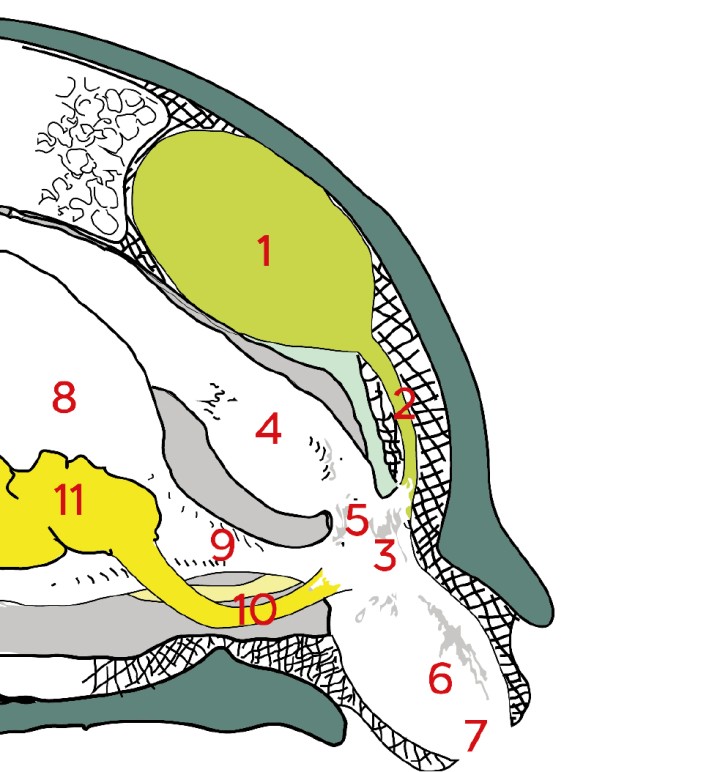

El órgano se divide en tres regiones (Fig. 1), delimitadas por pliegues:

– Coprodeo: el segmento anterior, continuación del colon distal.[ Boyer T, Innis C: Chelonial Taxonomy, Anatomy and Physiology. En Mader´s Reptile and Amphibian Medicine and Surgery (third ed), St Louis, Saunders Elsevier, 2019; 43-46. , Hnizdo J: Turtle anatomy and physiology. En Medical care of turtles and tortoises, Frankfurt, Edition Chimaira, 2011; 16-19. ]

– Urodeo: la sección media, donde desembocan los uréteres, la vejiga de la orina en aquellas especies que la tienen y los conductos del tracto genital. En algunas especies la desembocadura del uréter y del tracto genital están fusionadas y lo hacen a través de la papila urogenital.[ Boyer T, Innis C: Chelonial Taxonomy, Anatomy and Physiology. En Mader´s Reptile and Amphibian Medicine and Surgery (third ed), St Louis, Saunders Elsevier, 2019; 43-46. , Hnizdo J: Turtle anatomy and physiology. En Medical care of turtles and tortoises, Frankfurt, Edition Chimaira, 2011; 16-19. ]

– Proctodeo: es la parte final de la cloaca antes de abrirse al exterior. En los machos se encuentra el pene (en aquellas especies que lo poseen) y es donde se produce la cópula en el caso de las hembras.[ Boyer T, Innis C: Chelonial Taxonomy, Anatomy and Physiology. En Mader´s Reptile and Amphibian Medicine and Surgery (third ed), St Louis, Saunders Elsevier, 2019; 43-46. , Hnizdo J: Turtle anatomy and physiology. En Medical care of turtles and tortoises, Frankfurt, Edition Chimaira, 2011; 16-19. ]

Esquema de la anatomía del celoma caudal en un quelonio. Modificado de Medicine and surgery of tortoises and turtles.<sup>3</sup> 1: riñón; 2: uréter; 3: urodeo; 4: recto; 5: coprodeo; 6: proctodeo; 7: abertura cloacal; 8: vejiga; 9: uretra; 10: ductos genitales; 11: gónada.

Esquema de la anatomía del celoma caudal en un quelonio. Modificado de Medicine and surgery of tortoises and turtles.3 1: riñón; 2: uréter; 3: urodeo; 4: recto; 5: coprodeo; 6: proctodeo; 7: abertura cloacal; 8: vejiga; 9: uretra; 10: ductos genitales; 11: gónada.